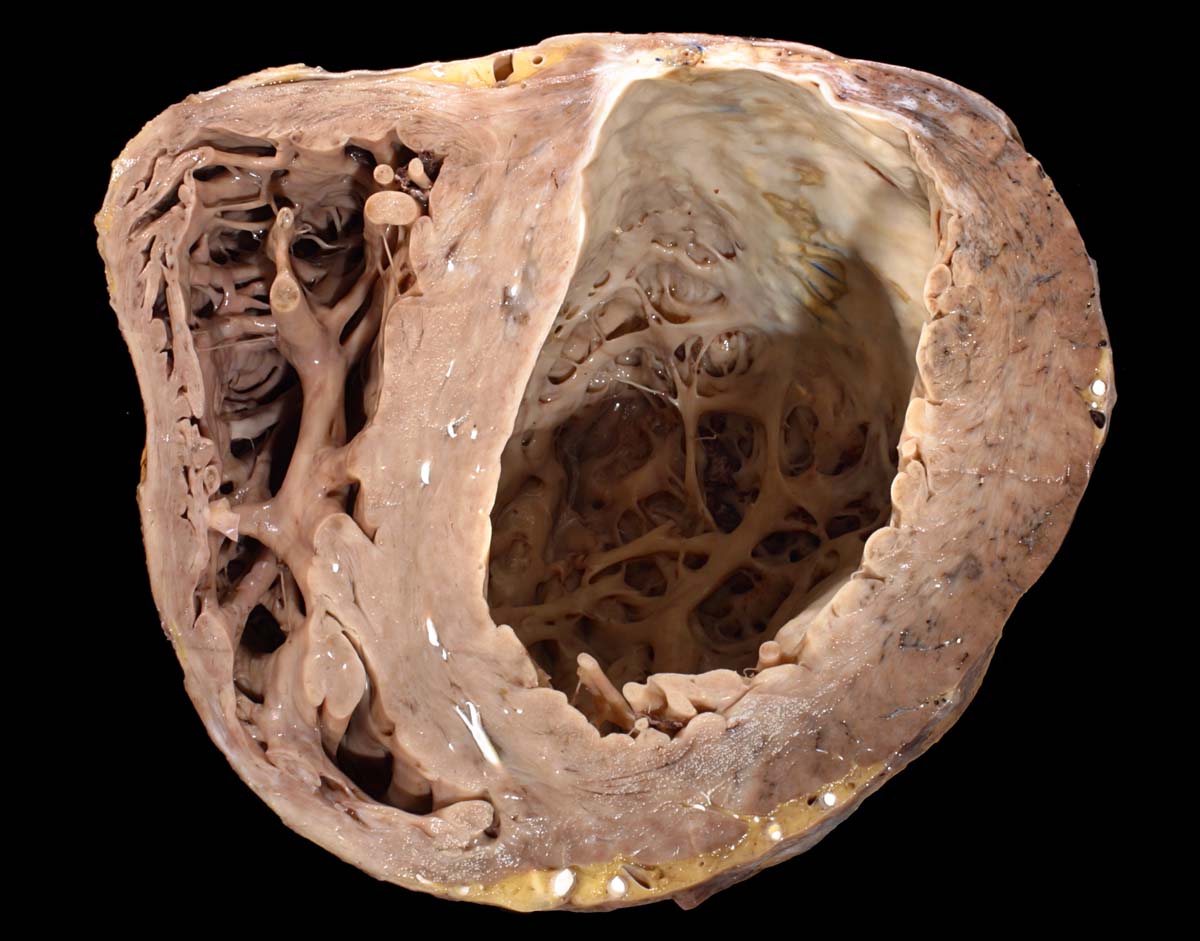

Eine restitutio ad integrum nach abgelaufener Myokardnekrose ist nicht möglich. Wird das Ischämieereignis überlebt, kommt es zu einer reparativen Regeneration mit Ersatz der Muskulatur durch kollagenreiches Narbengewebe. Dieser Vorgang setzt etwa ab dem 9. Tag nach Infarkt ein und dauert bis zur vollständigen narbigen Ausheilung bei transmuralem Infarkt etwa 50 Tage. Makroskopisch imponiert die Narbe als fasriges weisses derbes Areal. Von einem Infarkt spricht man, wenn die Nekroseareale einen Durchmesser von mindestens 3cm Durchmesser haben. Ab dieser Grösse kann klinisch das Bild eines Myokardinfarktes ausgelöst werden. Kleinere, makroskopisch sichtbare Narben werden als grobfleckige Myokardfibrose (> 873) (> 234) bezeichnet.

Im Bereich grösserer Narben ist das Myokard verdünnt. Bei 8% der transmuralen Infarkte entsteht im Bereich der Narbe ein Herzwandaneurysma (> 2088) mit oder ohne wandständige Thrombose (> 348). In 5-15% führen die Thromben zu systemischen Embolien. Von der Randzone der Aneurysmen gehen oft hartnäckige ventrikuläre Rhythmusstörungen aus. Grosse Narben führen zu einer Verminderung der Pumpleistung mit Herzinsuffizienz.